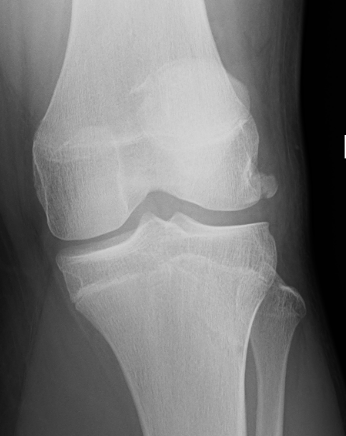

Xray

Look for osteochondral fractures

- AP xray: gutters

Loose body in lateral gutter